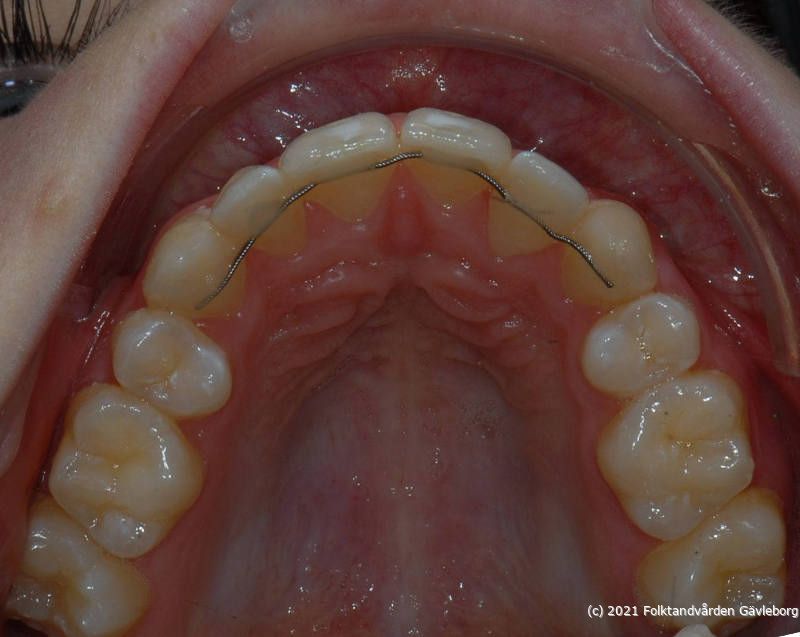

På ortodontiklinikerna diagnostiserar och behandlar vi bettfel på både barn och vuxna. Alla våra patienter kommer på remiss till oss. Vi behandlar bettfelen med fastsittande och avtagbar apparatur. Hos oss behandlas också de patienter som har avvikelser i käk- och ansiktsskelettet och som kräver tandreglering inför rekonstruktiv kirurgi. Vi har ett nära samarbete med allmäntandvård, privattandvård och övrig specialisttandvård i länet samt ett gott samarbete med Akademiska Sjukhuset i Uppsala när det gäller barn med olika syndrom och läpp-käk-gomdefekter. Våra specialistkliniker finns i Gävle och Hudiksvall.

Här nedan hittar du några exempel på vanligt förkommande behandlingar. Hittar du inget som passar det du vill visa, gå in på menyn ovan genom att föra musen över "Information". Navigera sedan till respektive apparatur. Klickar du på rubriken "Visa alla bilder" får du upp samtliga apparaturer som finns här.